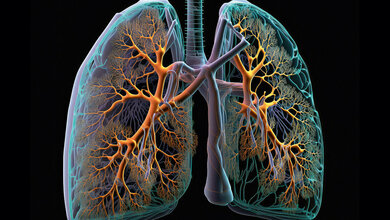

Laut Mukoviszidose e.V. sind in Deutschland mehr als 8.000 Kinder, Jugendliche und Erwachsene von der unheilbaren Erbkrankheit Mukoviszidose (Cystische Fibrose, CF) betroffen. Durch eine Störung des Salz- und Wasserhaushalts im Körper bildet sich bei Mukoviszidose-Betroffenen ein zähflüssiges Sekret, das Organe wie die Lunge und die Bauchspeicheldrüse irreparabel schädigt. Jedes Jahr werden in Deutschland etwa 150 bis 200 Kinder mit der seltenen Krankheit geboren. Die Krankheit führt zu einem fortschreitenden Verlust der Lungenfunktion und Atemnot, was die Lebenserwartung trotz verbesserter Behandlungsansätze noch immer deutlich senkt. Bereits vor zwei Jahren hatte eine Forschungsgruppe unter Leitung der Charité gezeigt, dass die Kombinationstherapie mit den drei Wirkstoffen Elexacaftor, Tezacaftor und Ivacaftor für einen großen Teil der Patientinnen und Patienten mit der Erbkrankheit Mukoviszidose wirksam ist, also die Lungenfunktion und Lebensqualität spürbar verbessert. Die Therapie kommt für knapp 90 Prozent der Mukoviszidose-Betroffenen infrage, die den häufigsten Gendefekt F508del haben.

Jetzt hat das Team um Prof. Dr. Marcus Mall, damaliger und aktueller Studienleiter, erstmals untersucht, inwiefern diese Therapie auch langfristig, das heißt über mindestens zwölf Monate hinweg, hilft. Dafür haben die Forscherinnen und Forscher das Sputum, das Atemwegssekret, genauer betrachtet. „Bei Patientinnen/Patienten mit Mukoviszidose ist der Schleim in den Atemwegen sehr zäh, weil er zu wenig Wasser enthält und die schleimbildenden Moleküle, die sogenannten Muzine, zu stark chemisch miteinander verklebt sind. Der daraus resultierende zähe Schleim verstopft die Atemwege, erschwert damit die Atmung und führt bei den Betroffenen zu einer chronischen bakteriellen Infektion und Entzündung der Lunge“, erklärt Prof. Mall, Direktor der Klinik für Pädiatrie mit Schwerpunkt Pneumologie, Immunologie und Intensivmedizin und des Christiane Herzog Mukoviszidose-Zentrums der Charité.

Die Wissenschaftlerinnen und Wissenschaftler zeigen in der aktuellen Studie, dass die Dreifachtherapie mit Elexacaftor, Tezacaftor und Ivacaftor bei Patientinnen und Patienten mit Mukoviszidose dafür sorgt, dass das Atemwegssekret weniger zäh ist und die Entzündung und die bakterielle Infektion in der Lunge abnehmen. „Und das über die gesamte Dauer der Studie von einem Jahr. Das ist deshalb so bedeutsam, weil frühere Medikationen wieder zu einem Anstieg der Bakterienlast in den Atemwegen geführt hatten“, erläutert Dr. Simon Gräber, ebenfalls von der Klinik für Pädiatrie mit Schwerpunkt Pneumologie, Immunologie und Intensivmedizin der Charité und Co-Leiter der Studie. An dieser nahmen 79 Jugendliche und Erwachsene mit Mukoviszidose und einer chronischen Lungenerkrankung teil.